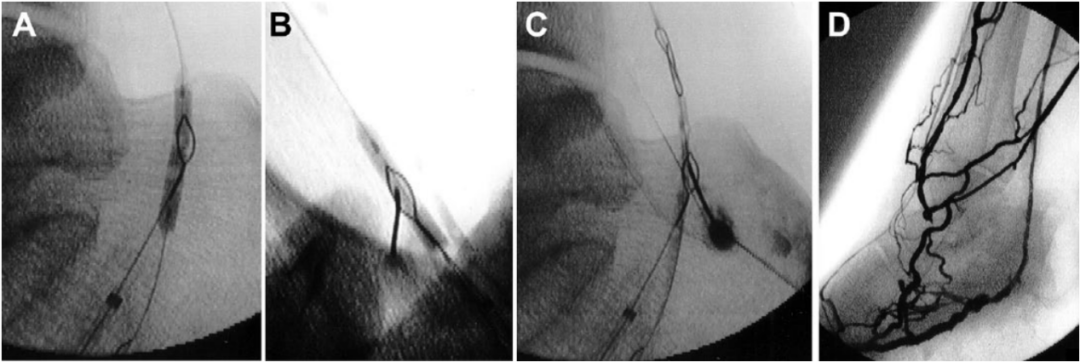

①若静脉位于动脉前方:将针头插入,使其指向圈套器环并穿过静脉的两壁和圈套器环。此时,收紧圈套器环以确认针头已穿过。一旦针头离开静脉,便进一步推进,直至到达动脉并刺穿球囊导管。将0.018英寸的导丝穿过针头并置入穿刺的球囊导管内。球囊导管完全抽出,同时保持导丝卡在内部,以便静脉通路的导丝可以通过股动脉鞘向外伸出。4F支撑导管通过导丝向前推进至静脉,引入第二根0.014英寸导丝至导管并推进,直至它清楚地定位于静脉腔内以确认血管腔内的位置。(见图3和图4)

图3. 静脉动脉化简化技术示意图。(A)插入针头,穿过静脉的两层壁和圈套器环。(B)针头到达动脉并刺穿球囊导管。将一根0.018英寸的导丝推进并放置在刺穿的球囊内。(C)撤出球囊导管,保持导丝卡在球囊内,以便回撤通过股鞘将其引出体外。(D)顺行推进支撑导管。(E)推进0.014英寸的导丝,直至其明确位于静脉腔内。(F)动静脉吻合口血管成形术。

图4. 静脉动脉化简化技术术中造影(A) 圈套器和充盈球囊重叠。(B) 22-G微穿刺针经皮推进,穿过球囊和圈套器环。(C) 取出球囊导管,同时保持导丝在其中。(D) 静脉动脉化的血管造影图像。